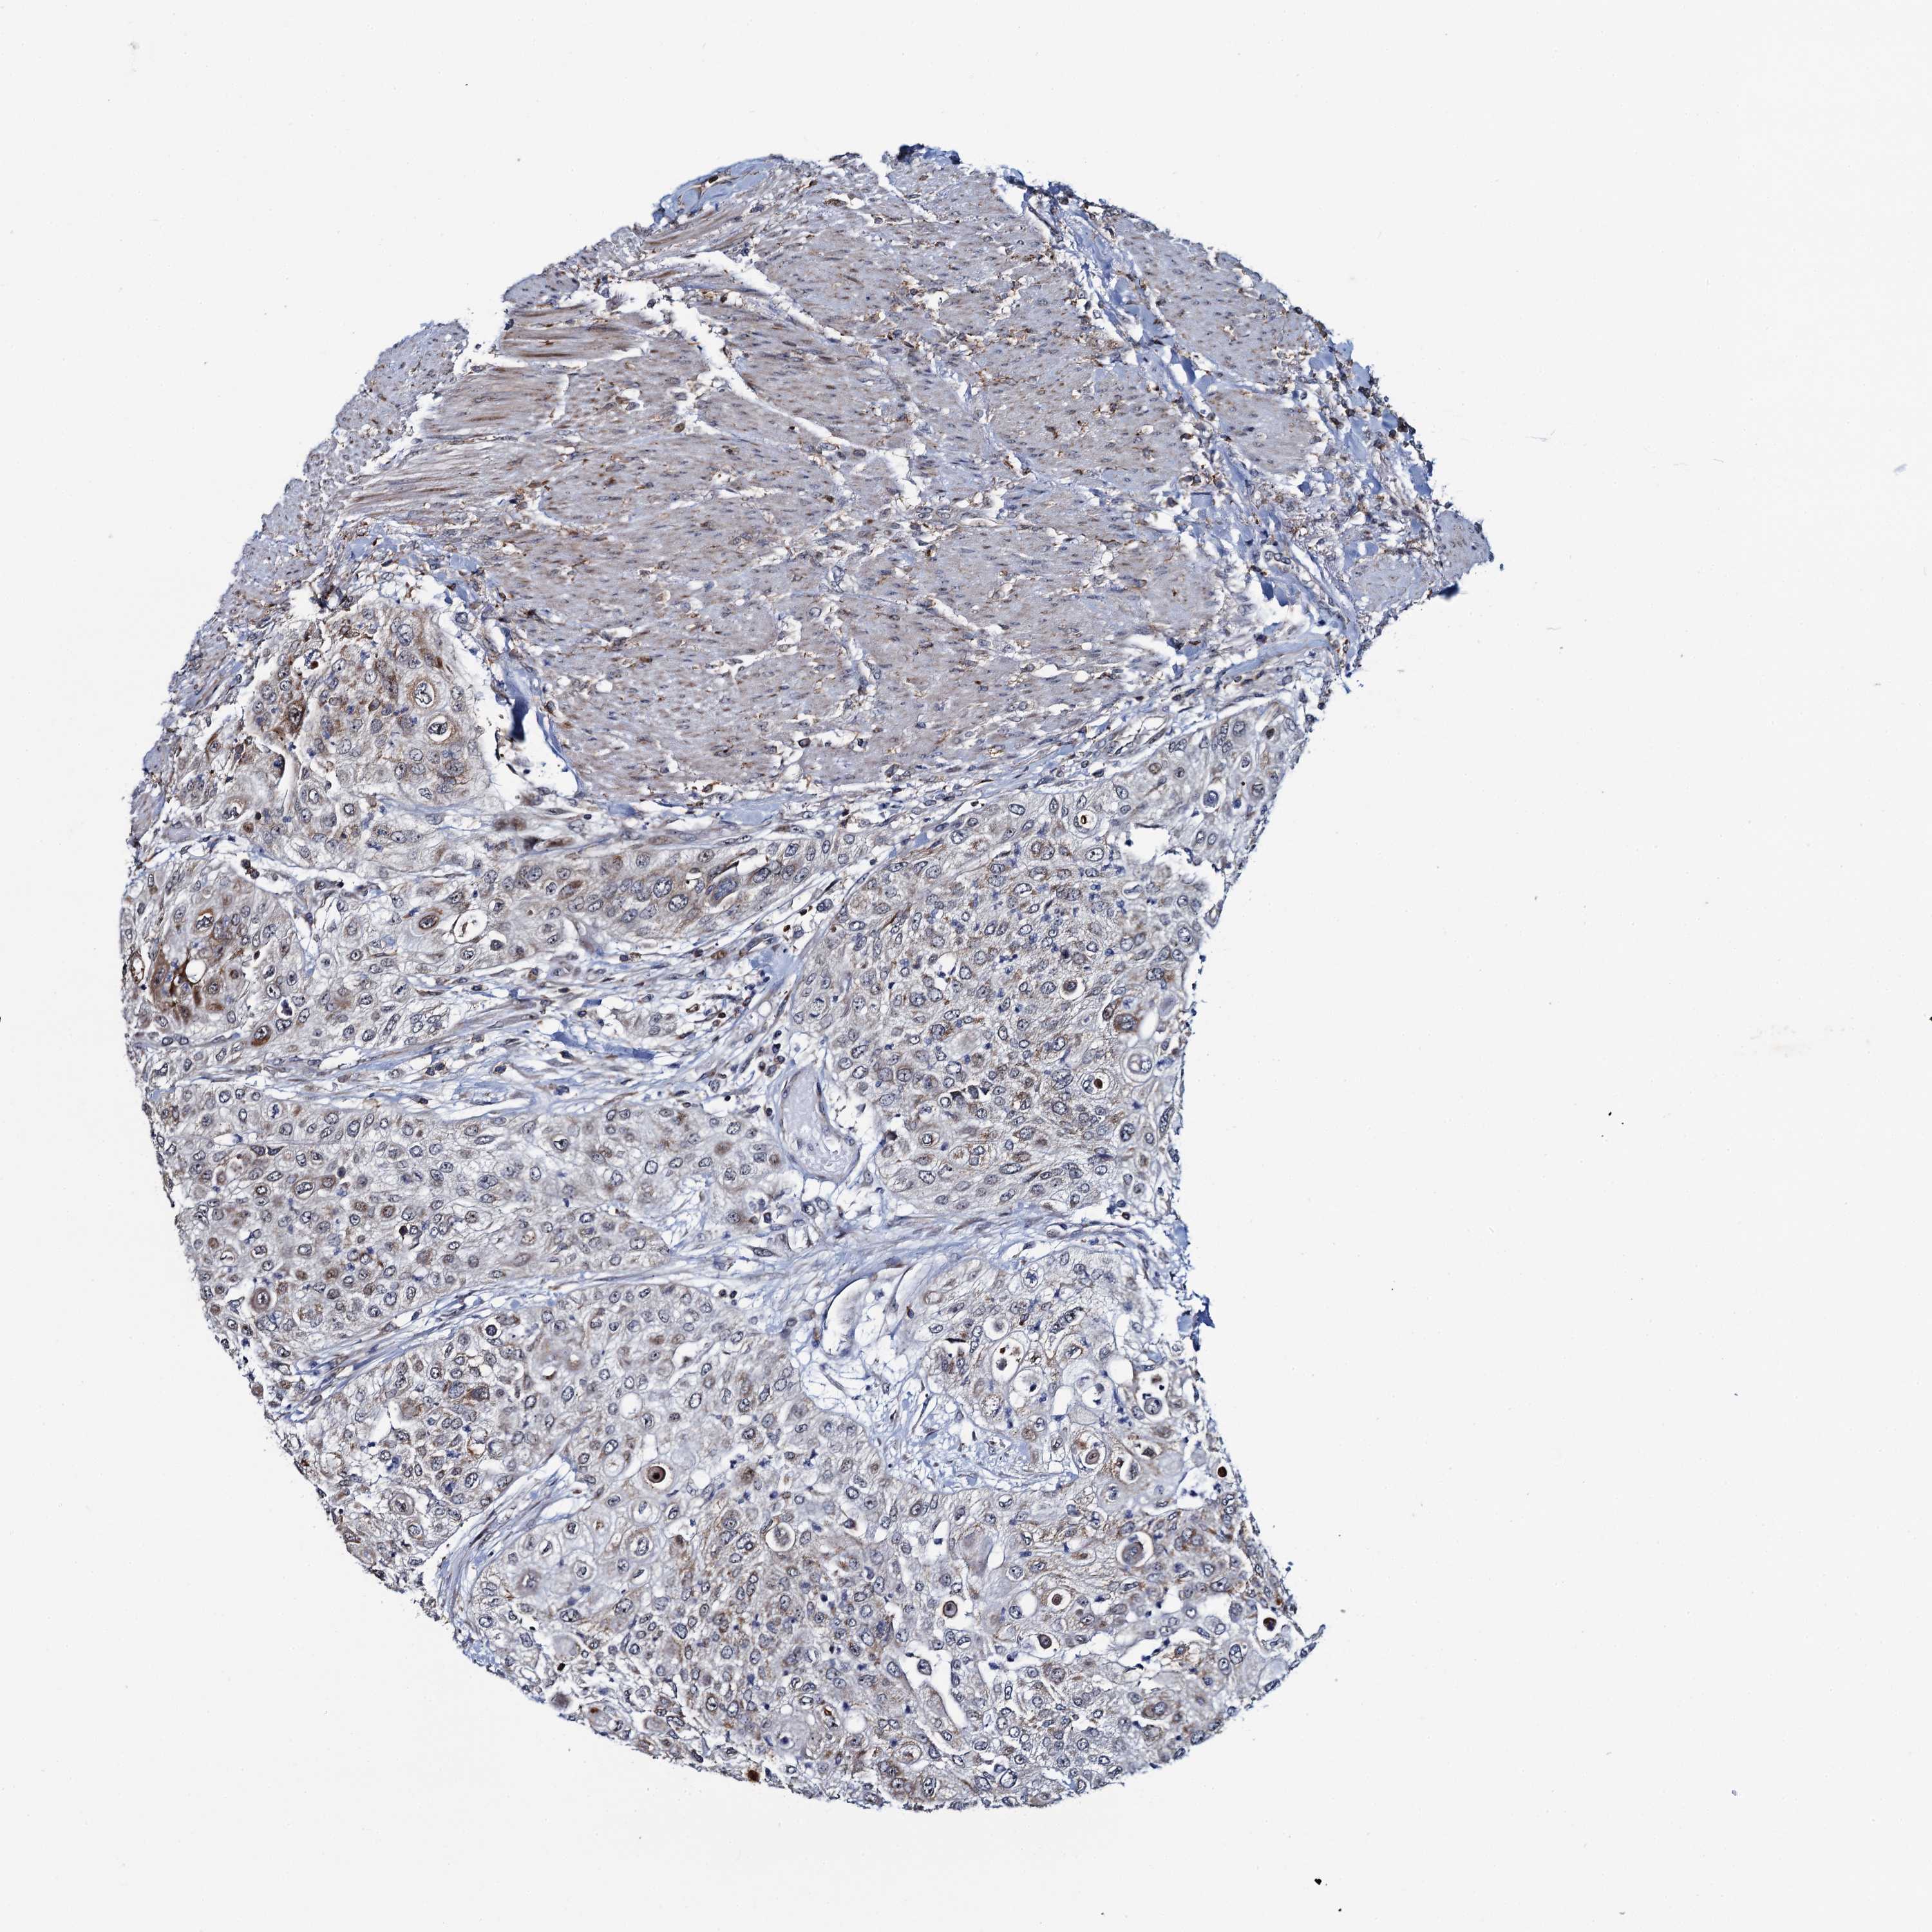

UROTHELIAL CANCER - Protein expressioni

A mouse-over function shows sample information and annotation data. Click on an image to view it in a full screen mode. Samples can be filtered based on level of antibody staining by selecting one or several of the following categories: high, medium, low and not detected. The assay and annotation is described here.

Note that samples used for immunohistochemistry by the Human Protein Atlas do not correspond to samples in the TCGA dataset.

Antibody stainingi

Antibody staining in the annotated cell types in the current human tissue is reported as not detected, low, medium, or high, based on conventional immunohistochemistry profiling in selected tissues. This score is based on the combination of the staining intensity and fraction of stained cells.

Each image is clickable and will lead to virtual microscopy that enables deeper exploration of all samples and also displays staining intensity scores, fraction scores and subcellular localization as well as patient and tissue information for each sample.

Antibody HPA040598

Antibody HPA040958

Staining

High

Medium

Low

Not detected

Intensity

Strong

Moderate

Weak

Negative

Quantity

>75%

75%-25%

<25%

None

Location

Nuclear

Cytoplasmic/membranous

Cytoplasmic/membranous,nuclear

Urothelial carcinoma, High grade

Urothelial carcinoma, Low grade